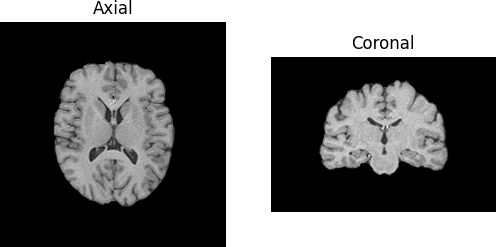

We have fetched the T1 volume. Now we will look at the axial and coronal slices of the image.

T1-weighted image of healthy adult.